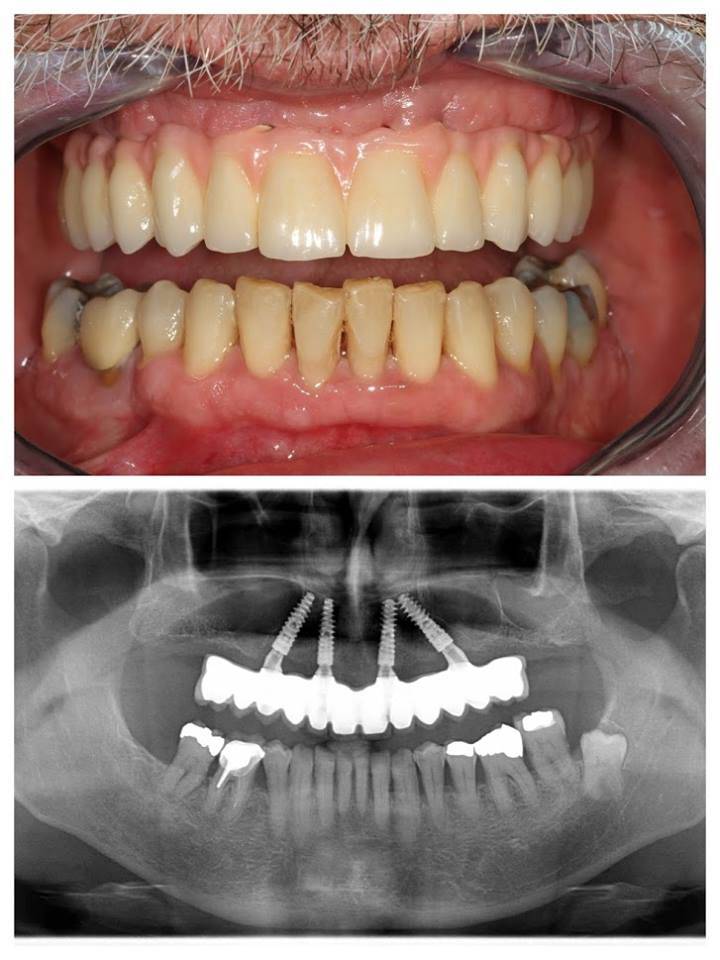

All-on-4 előtte-utána

Az első konzultáció egy átfogó klinikai és radiológiai vizsgálatból áll. Panoráma röntgent és 3D CT felvételeket készítünk. A szájsebész kielemzi a felvételeket és pontosan megtervezi az eljárást. Ha minden kész, Önnek csak be kell ülnie a fogorvosi székbe. Ezután magasan képzett szakembereink maximális odafigyeléssel, empátiával végzik munkájukat .

Először helyi érzéstelenítést adunk, majd 4 titánium implantátumot helyezünk be. Kettőt egyenesen az állcsont elülső és kettőt ferdén a hátsó területére. Ezek fogják támasztani az állkapocsba rögzített teljes hidat. Az így behelyezett híd természetesnek hat, hosszú ideig jól illeszkedik, nem mozog, ezáltal garantálja a természetes fogak funkcionalitását és harapási minőségét.